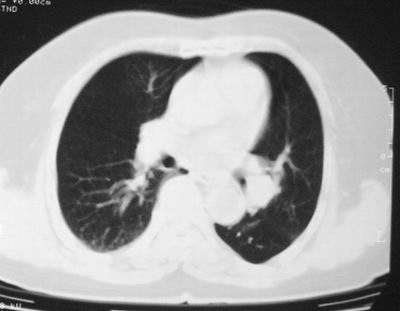

患者,女,64岁,4年前左腮腺"多形性"腺瘤手术治疗史.现复查胸部ct见左下肺块状影,该影与原左腮腺手术是否有联系?

本次复查胸部ct

左下肺软组织块影,有分叶、毛刺、空泡及胸膜牵拉征,左下肺周围性肺癌。

左肺下叶周围型肺癌,支持!(软组织肿块+分叶+毛刺+空泡+胸膜凹陷征)

左下肺软组织密度影,可见分叶,边缘可见毛刺征,胸膜增厚,强烈要求左下肺周围型肺癌